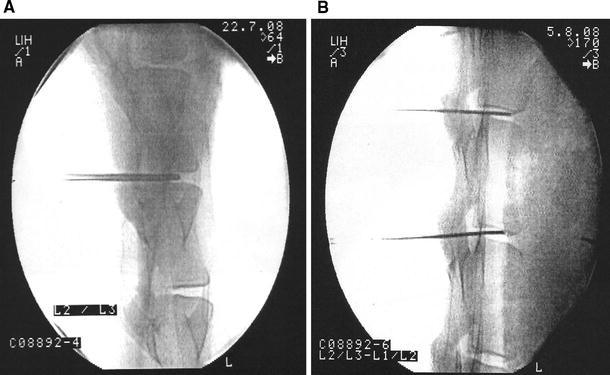

Anesthetized animals (butorphanol 0.1–0.2 mg/kg i.v./diazepam 0.1–0.2 mg/kg, followed by thiopental 15 mg/kg and then by 1 % propofol 5–15 ml, level maintained using isoflurane/oxygen) were positioned ventrally upright on the operating table, shaved in the lumbar spine area, with the area being disinfected with betadine®:water = 1:1. IVD tissue (consisting of combined annulus and nucleus tissue, as in human patients) was harvested under X-ray control using a 4-mm-diameter biopsy needle from discs L1-2, L2-3 and L3-4 (Fig. 1a). The needles were placed on to the discs, the core nail removed and the hollow needle inserted into the discs. The harvested tissue was transported in sterile containers to the tissue culture facility. In parallel, 50 ml of blood was drawn and converted to serum for the autologous tissue cultures.

Fig. 1

figure 1

a C-arm X-ray image. 4-mm biopsy needle positioned into disc L2-3. The radiological image is a print out from the C-arm instrument, perpendicular view. b C-arm image: 18 gauge needles positioned into L1-2 and L2-3 prior to the injection

Surgical implantation into and recovery from sheep

The sheep received prophylactic antibiotic treatment: 30,000 IU penicillin/kg and 6 mg gentamycin/kg at 30 min prior to surgery and twice over 3 days postsurgically, plus tetanus prophylaxis 500 IU tetanus toxin/sheep. Animals were anesthetized and the area for operation was shaved and disinfected as before. The injection needles (18 gauge, 15 cm) for re-injecting the cells were pre-positioned under radiological control (C-arm instrument) (Fig. 1b).